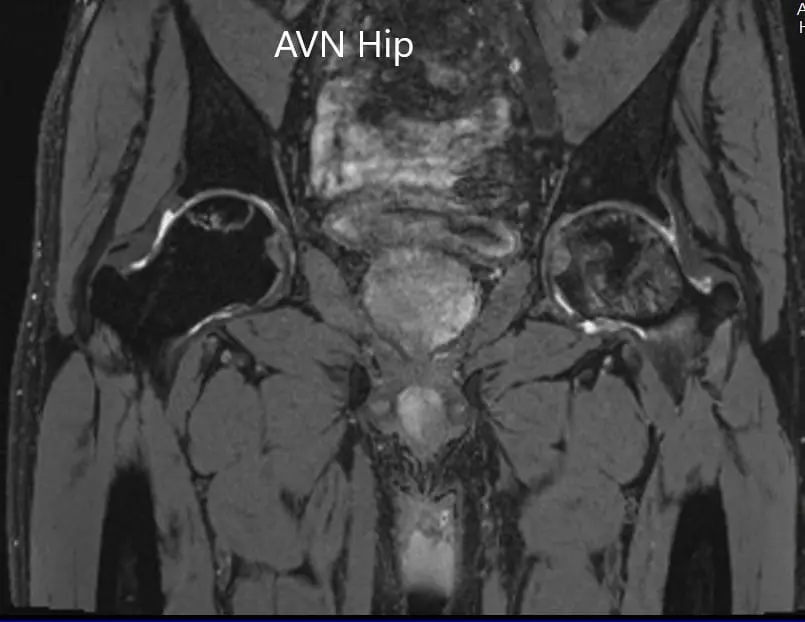

The left femoral head was collapsed with irregular contour and shows areas of altered signal intensity with a line of demarcation. Hypointense areas both on T1WI & T2WI seen in head suggestive of sclerosis. Surrounding marrow edema seen. A small amount of joint effusion with few osteophytes seen. The joint space was preserved.

The right femoral head shows areas of altered signal intensity with serpiginous demarcation line visualized, Hypointense areas both on T1WI & T2WI seen in head suggestive of sclerosis. The femoral head contour was normal. Surrounding marrow edema is seen. Small joint effusion is seen. Joint space is preserved.

Percentage necrotic areas in bilateral femoral heads are approximately 60-70 %.

T2WI coronal section of MRI showing AVN hip.